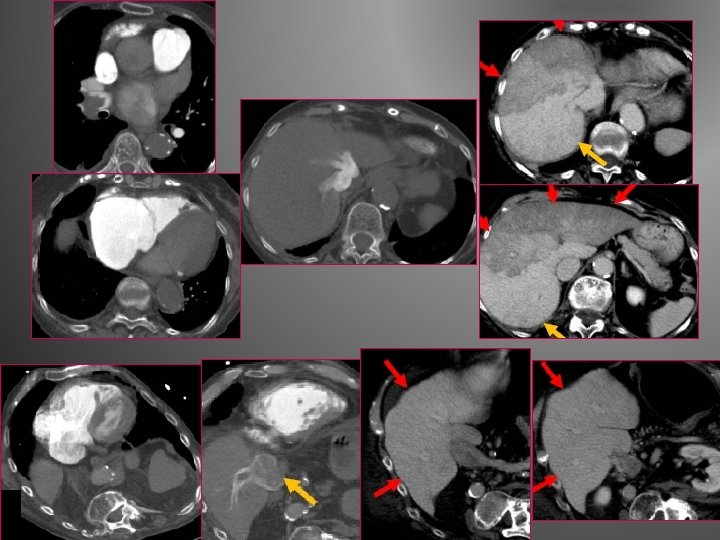

� Emboles tumoraux: -Le plus svt embolie périphérique sous segmentaire -Plus rarement EPA proximale (envahissement cave inférieur de CHC, d’ADK rénal ou de chorio carcinome) -Rehaussé par le PDC

EPA tumorale sur tumeur de Grawitz bilatérale/ envahissement cave inférieur EPA sur tumeur de Grawitz droite/ envahissement cave inférieur

EPA bilatérale sur CHC EPA sur CHC, envahissement de VCI, TP et AD